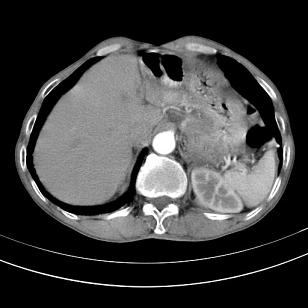

标题: 男,65岁,反复右上腹痛, [打印本页]

标题: 男,65岁,反复右上腹痛,

胃镜提示十二指肠占位